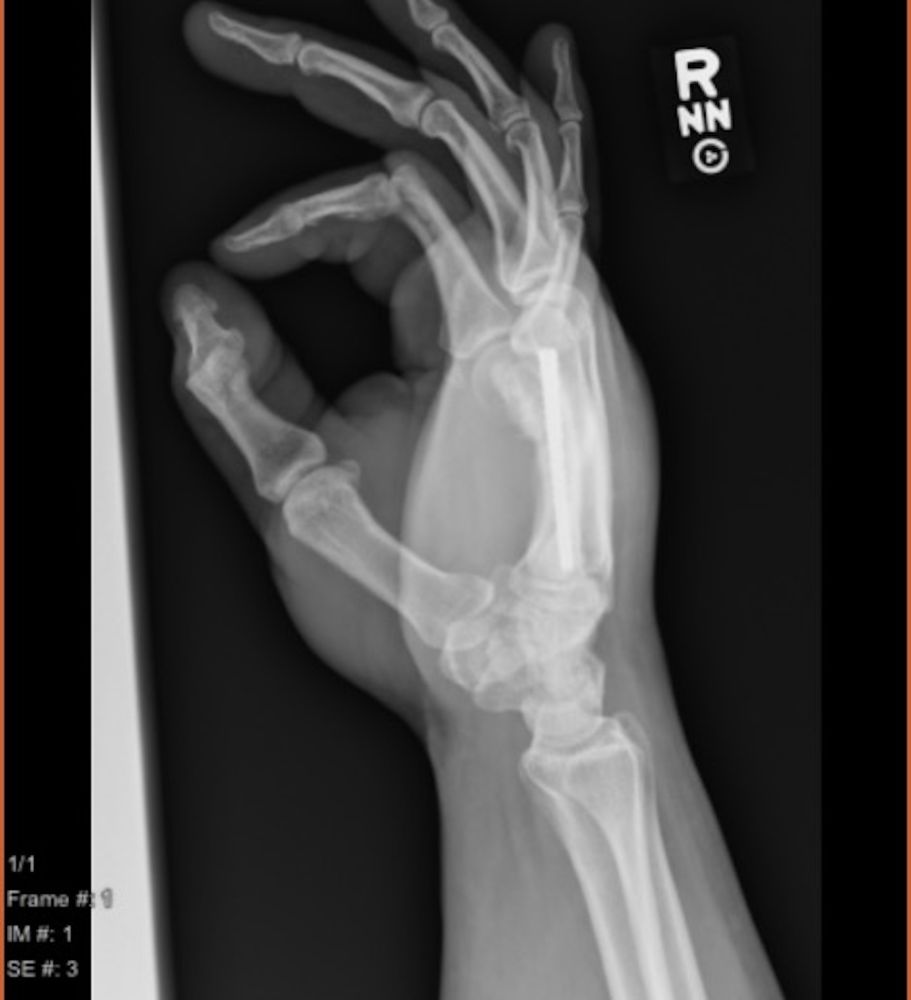

A 39-year-old male presented with a right index finger metacarpal neck malunion with a 30-degree extensor lag and an ulnar malrotation of the digit (Figures 1 and 2) after a fracture 8 months prior. The patient underwent right index finger metacarpal lengthening using iliac crest tricortical bone autograft, right index finger metacarpal joint dorsal and volar capsulectomy, as well as extensor tenolysis and A1 pulley release. A single-stage metacarpal lengthening was achieved with intercalary structural iliac bone graft and intramedullary screw. At 2-week follow-up, the patient had achieved length restoration that resolved extensor lag, reestablished cascade, and had appropriate rotation. At 3-month follow-up, the patient had achieved osseous union and maintained normal cascade of his hand with the ability to make a composite fist. In this article, we present this novel technique for single-stage metacarpal lengthening.

Figure 2. Preoperative oblique X-ray image of right hand with index finger metacarpal malunion.